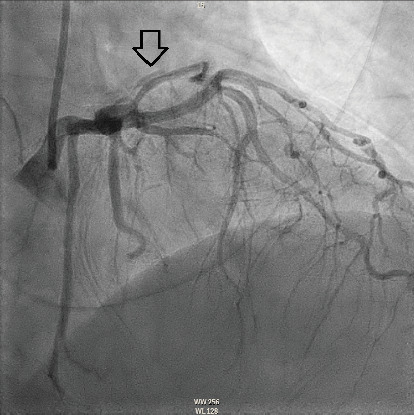

The management of spontaneous coronary artery dissection (SCAD) presents challenges and uncertainties. We present a case of a 54-year-old woman who developed SCAD in the three primary coronary artery territories including the distal left anterior descending artery (LAD), a diagonal branch, the first and second obtuse marginals (OMs), and the midright coronary artery (RCA). She was managed conservatively without procedural intervention, and follow-up coronary angiography demonstrated complete recovery.

自发性冠状动脉夹层(SCAD)的治疗存在挑战和不确定性。我们报告了一例54岁的女性,她在三个主要冠状动脉区域发生了SCAD,包括左前降支远端,对角分支,第一和第二钝缘(OMs)和右冠状动脉(RCA)。患者接受保守治疗,无手术干预,随访冠状动脉造影显示完全恢复。